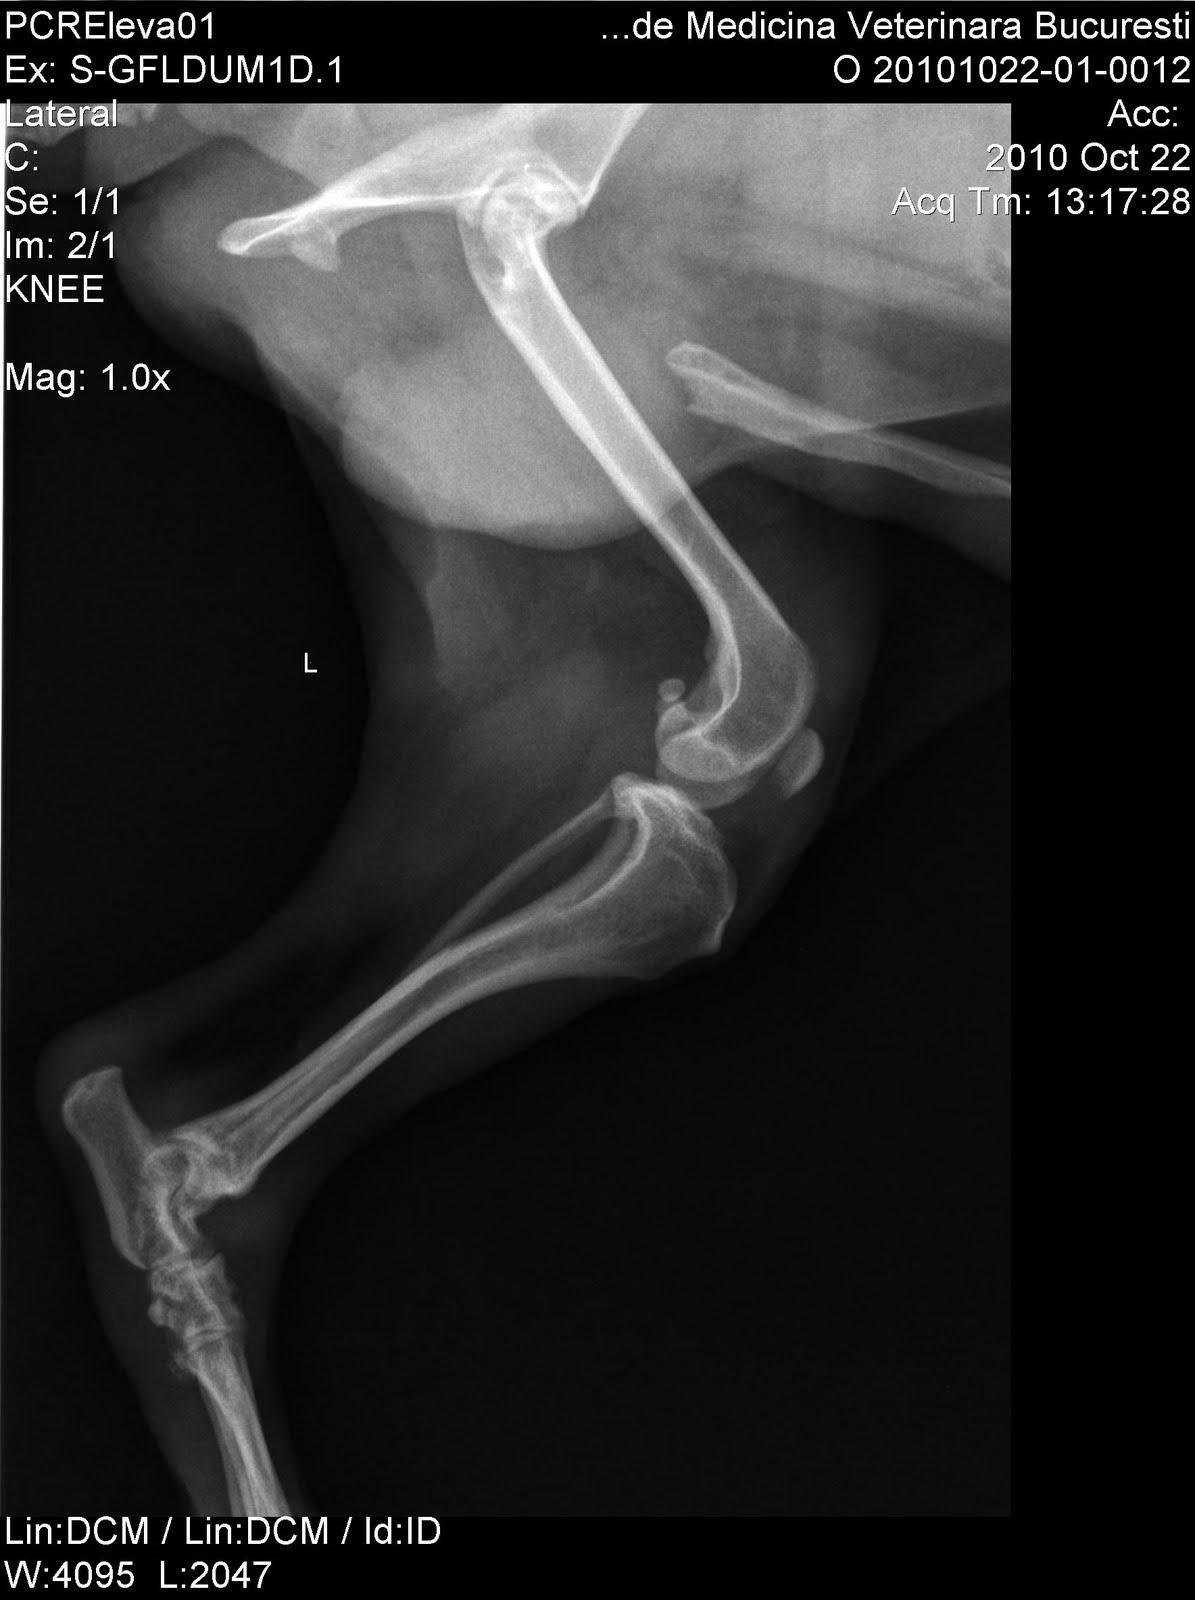

A vet told me that the rear paws are transaparente bones, demineralized, perhaps from the Prdenisone took. And dexamethasone.

At the same time his doctor, a nice young lady and saw all the radiographs taken me a bad evolution of the spine. With my words, he saw a hip arthritis, quite severe, small bones of the paws transparency and a lack of space between vetrebere a certain place.

In April 2010 he falled down from an armchair, he was screaming many minutes because of the pains and for a hour he was paralised. After that he started to have problems with his walking. He is making efforts on walking. Now he doesn't walk almost at all. He recovered from the paralisis stage but still got problems with the walk. One month after this he's got babesiosis who was treated and he felt better. A long time he got fever and muscle and articular pains and that's why the vets here thought it is Lyme. He took a lot of anthibiotics, a lot of doxicycline but without any results. Neither the Lyme tests showed he is got the disease.

I attach some X rays and some pictures of him. Maybe you will feel pitty for us and give advice what to do.

Bellow are his X rays and his photos.